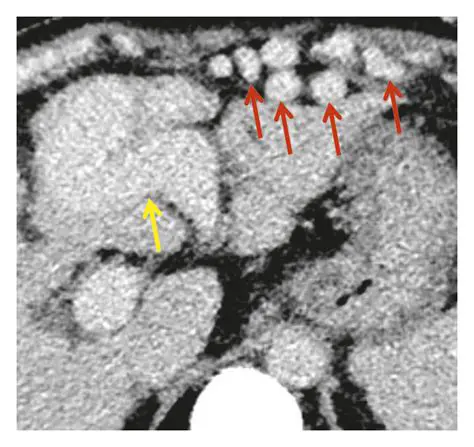

The Relationship Between a Recanalized Umbilical Vein and Liver Conditions Oct 13, 2025 by leolavanderia.com.br 58 views